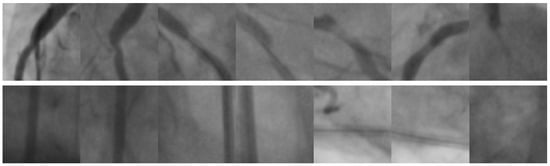

For the experiments, two distinct publicly available image databases of coronary stenosis cases were used. The first image database contains 608 images corresponding to regions of coronary angiograms, which were properly validated by cardiology experts [46]. Each image size is pixels. The number of positive and negative cases is 304 for each. Figure 9 illustrates a sample of 14 images containing positive and negative coronary stenosis cases.

Figure 9.

Image samples taken from the Stenosis608 [46] image database. The first row presents positive coronary stenosis cases. Consequently, the second row corresponds to negative coronary stenosis cases.